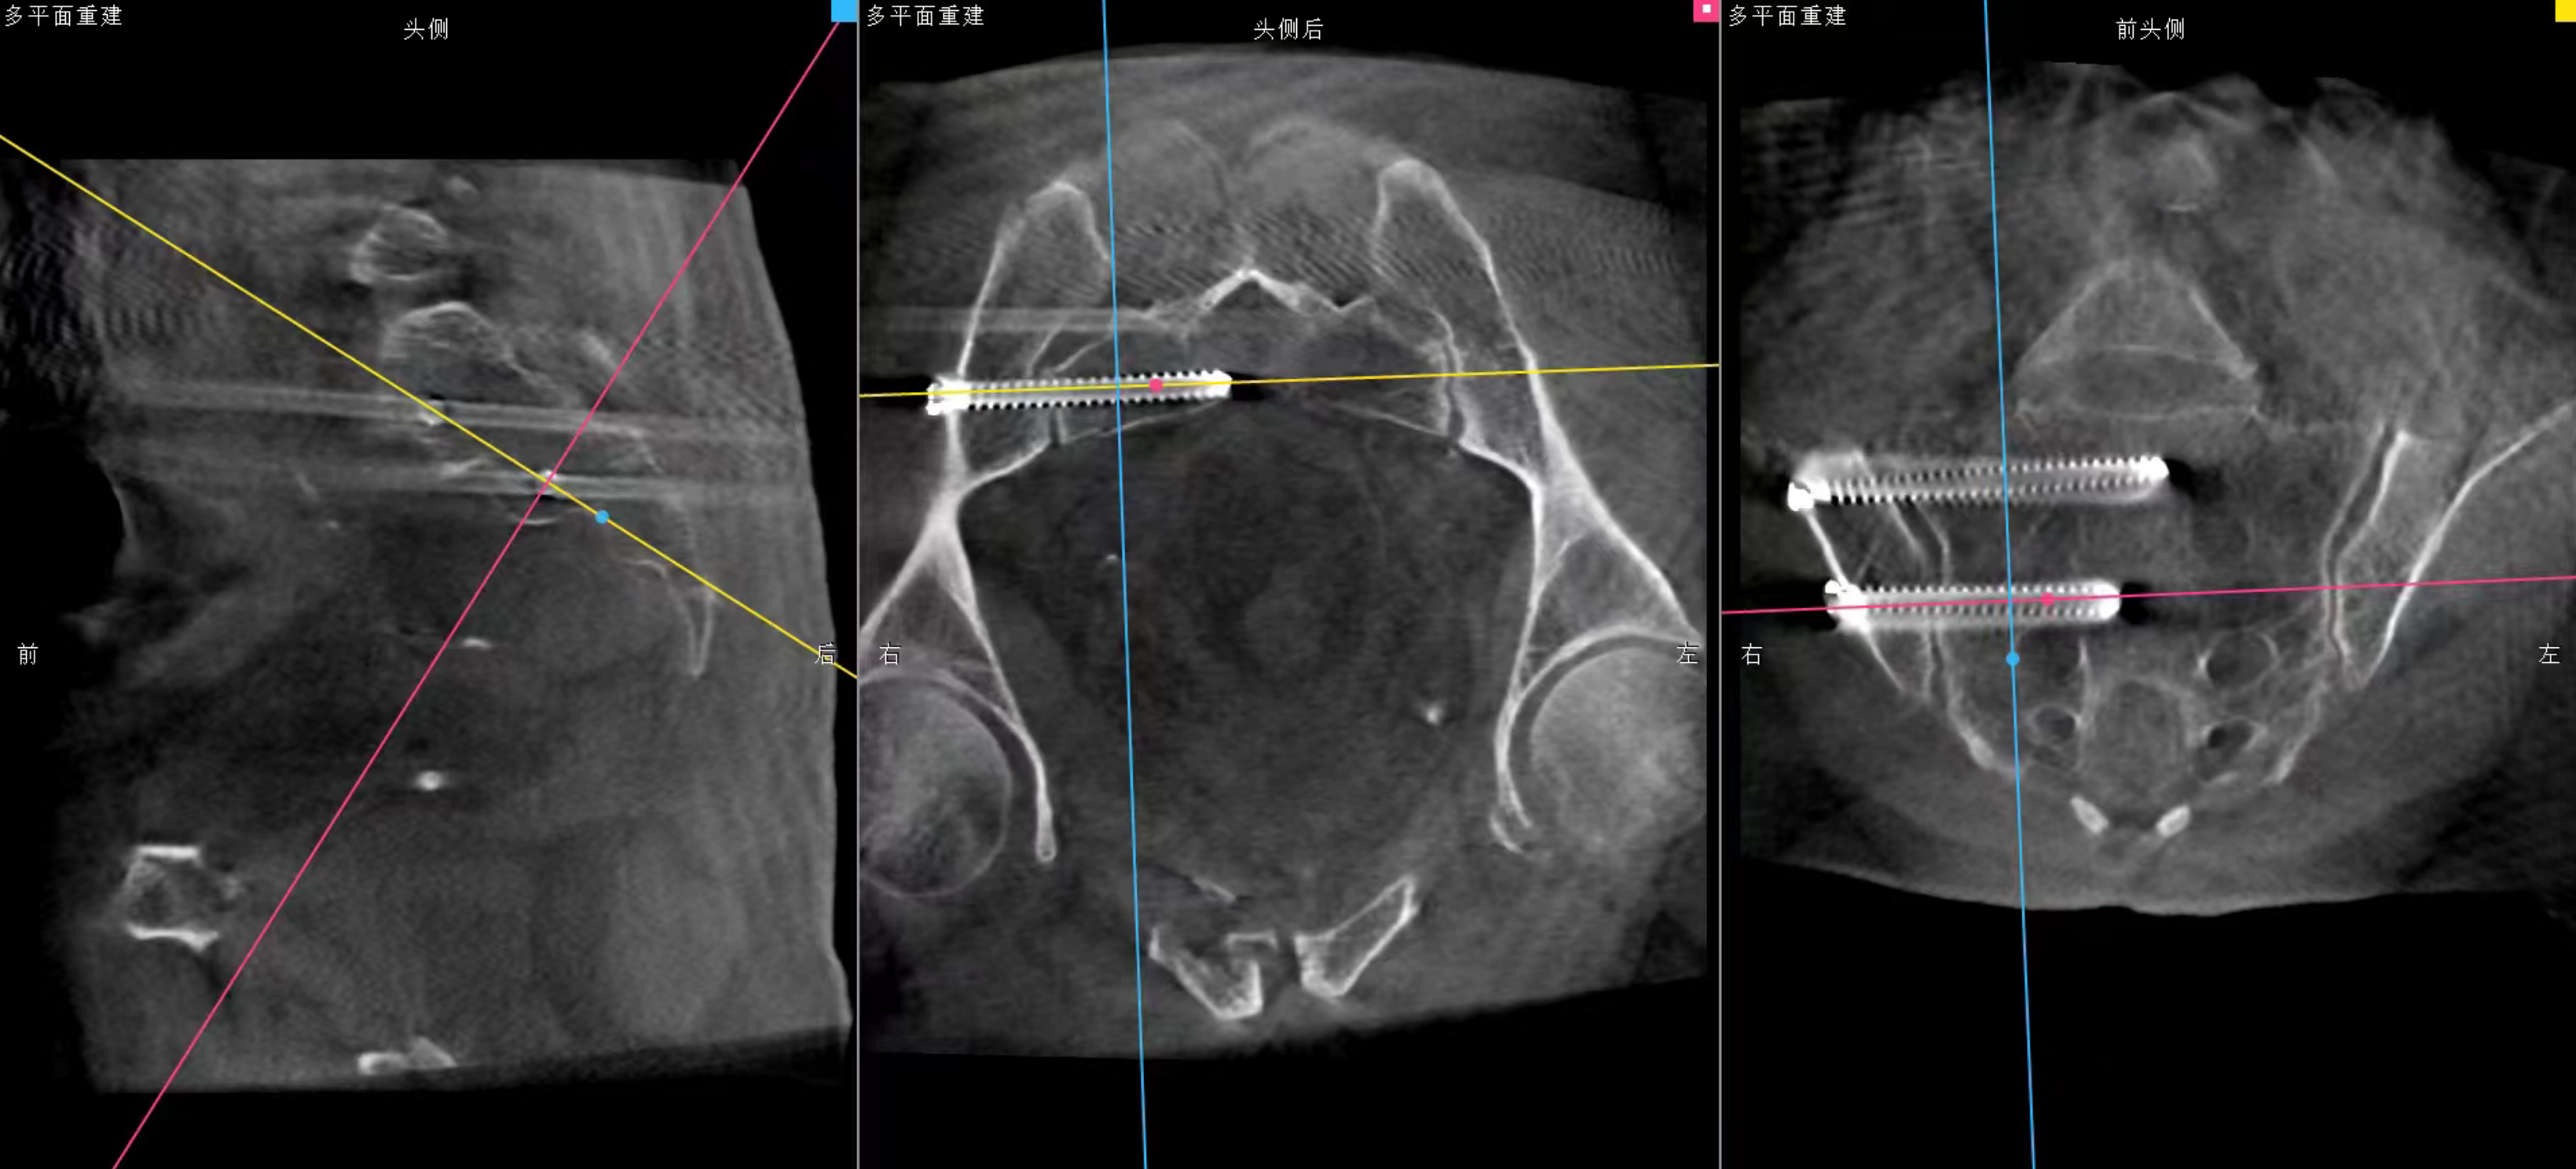

手术前,团队通过三维C臂机采集患者骨盆三维影像数据,上传至天玑机器人手术规划平台。系统自动完成影像配准后,医生在虚拟界面精准规划螺钉植入路径,模拟机械臂运动轨迹,确保避开血管神经等关键结构。

术中,机器人机械臂在光学追踪系统引导下自动调整至预设位置,亚毫米级定位精度可实时修正手术偏差,避免人为操作误差。医生仅通过4个1cm左右的微小切口,经皮置入导针、空心螺钉和infix螺钉,便完成了骨折端的稳定固定。

整个过程无需广泛剥离软组织,术中出血量较传统开放手术减少90%以上,且医护人员无需暴露在X射线辐射区域,实现了医患双重安全保障。术后影像学检查显示,骨折复位优良,螺钉位置完全符合术前规划,未出现任何血管神经损伤并发症。